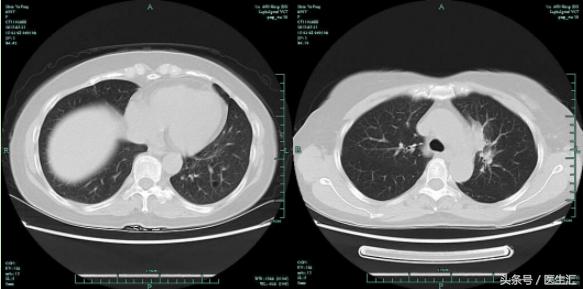

05-21CT:

CT出现左上肺病灶